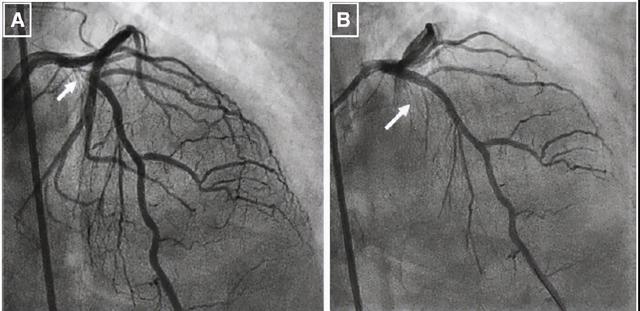

然后注入造影剂,医生在X光照射下可以直接观察到血管有无堵塞,血管堵塞的程度和部位,帮助医生更准确地评估病变,为治疗方式提供依据和指导。

所以,冠脉造影是冠脉狭窄诊断的“金标准”,算得上一种“终极武器”,让医生快速对症下药,直击敌人要害。